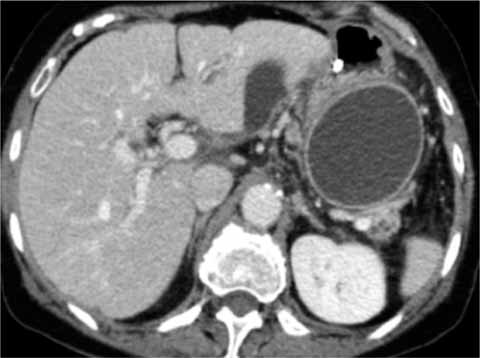

Pseudocyst is a common complication of acute and chronic pancreatitis. People with chronic pancreatitis can also get pseudocysts. A pancreatic pseudocyst is a circumscribed collection of fluid rich in pancreatic enzymes blood and necrotic tissue typically located in the lesser sac of the abdomen. Pseudocyst is a common complication of acute and chronic pancreatitis. While spontaneous resolution of acute pseudocysts is frequent in approximately 50 of cases acute pseudocysts progress to chronic pseudocysts. It can be caused by injury or trauma to the pancreas but the most common cause of pancreatic pseudocysts.